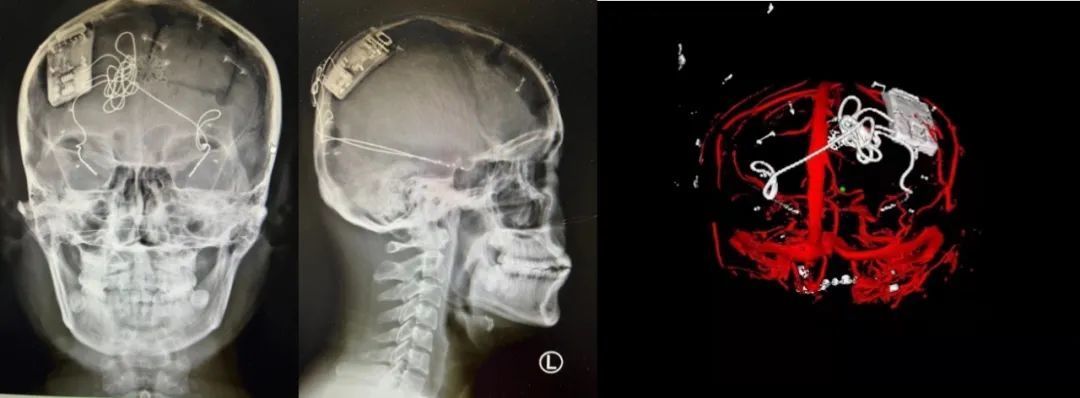

本次手術(shù)過程順利,術(shù)中刺激器各項指標(biāo)均工作正常,術(shù)后重建顯示電極位置精準(zhǔn),腦電信號清晰?;颊邽槟行裕朐汉笤\斷為雙側(cè)顳葉癲癇,此類癲癇為開顱手術(shù)的相對禁忌癥,在藥物無法控制的情況下,傳統(tǒng)治療效果欠佳 。

術(shù)前經(jīng)過宣武醫(yī)院癲癇多學(xué)科專家團(tuán)隊詳細(xì)的臨床評估,包括視頻腦電監(jiān)測、頭顱磁共振及三維 CT 掃描、腦核醫(yī)學(xué)檢查等,全面評估了患者病情及致癇灶定位情況。

由于患者臨床診斷為雙側(cè)顳葉癲癇伴海馬硬化,無法通過致癇灶切除等傳統(tǒng)外科手術(shù)方式獲益,決定進(jìn)行閉環(huán)反應(yīng)性神經(jīng)刺激系統(tǒng)植入手術(shù)治療。并根據(jù)閉環(huán)神經(jīng)刺激技術(shù)特點,為患者“量身定制”植入方案,尤其是電極植入位點和脈沖發(fā)生器固定部位等,為手術(shù)的順利實施奠定了良好基礎(chǔ)。

團(tuán)隊根據(jù)術(shù)前計劃,在手術(shù)機(jī)器人輔助下完成雙海馬長軸電極及 IPG 植入,術(shù)后重建顯示電極位置精準(zhǔn),腦電信號清晰。術(shù)后第二天,患者即下床活動,身體狀況恢復(fù)良好。